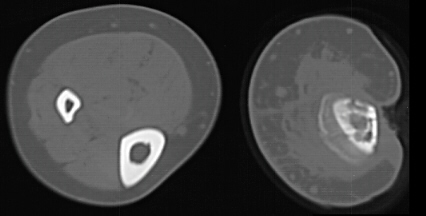

AP and lateral views of the right lower extremity revealed a Salter Harris III proximal tibial fracture with intraarticular extension into the medial and lateral tibial plateaus. The epiphysis was anteriorly displaced on the metaphysis.

The patient presented to A.I. DuPont 15 days later (103 days after injury) with serosanguinous drainage from the upper portion of his lateral wound. Irregular areas of sclerosis and lucency of the tibia on plain films and CT as well as irregular uptake on bone scan suggested areas of necrotic bone and chronic osteomyelitis. A hand film showed a bone age of 17 and scanogram documented a 2 cm leg length discrepancy. A lateral cortical tibial sequestrum gradually demarcated. He was followed for a year without lasting resolution of his drainage and underwent sequestrectomy and open packing of the wound.